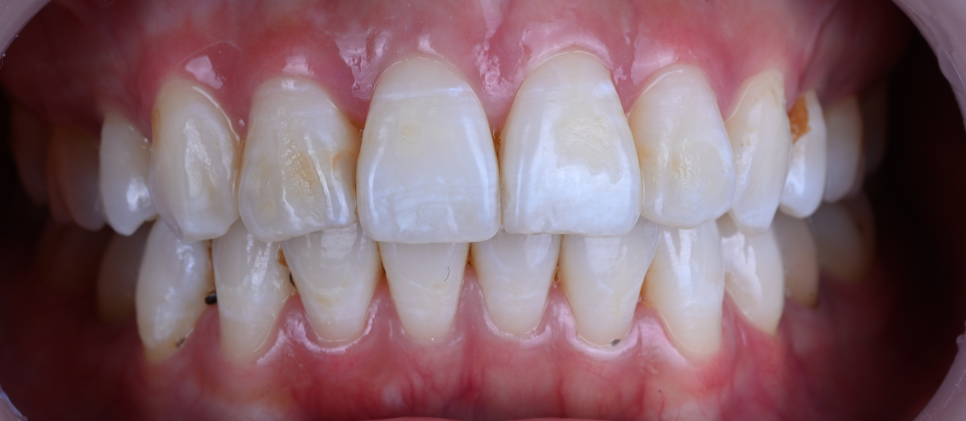

삐뚠치아 라미네이트

환자분의 동의하에 제공한 사진입니다

결과에 매우 만족하셨습니다.

처음에는 윗 치아만 진행하셨다가

변화에 대한 만족도가 높아

아래 치아까지 추가로 진행하셨습니다.